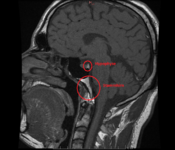

Weil ich Angst habe das mein Hirn von Schwermetalle geschädigt ist, und die Radiologie es nicht sieht ( weil die Microweiße Punkte im Hirn keiner Bedeutung zuweisen, diese sich aber über kurz oder Lang vergrößern können) habe ich die CD's der beiden MRT's aus den letzten beiden Jahren angefordert und möchte mittels Daunderers Bildmaterial mein Hirn mal vergleichen. Vielleicht erkenne ich ja Auffälligkeiten.